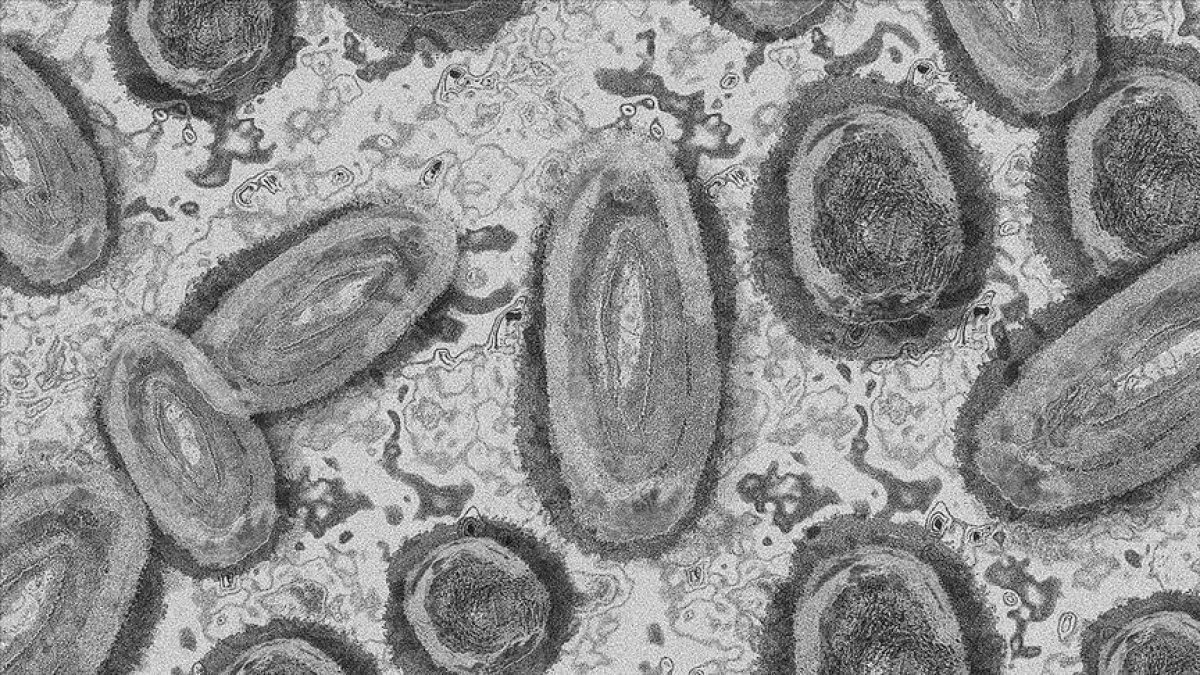

Endemik bir virüsün neden olduğu nadir hastalıklardan maymun çiçeği, Kongo ve Batı Afrika türü olmak üzere 2'ye ayrılıyor.

Genellikle hayvandan insana ve nadiren insandan insana yakın temasla bulaşan virüs, vücutta yüksek ateş ve kaşıntılı kabarcıklara yol açabiliyor.